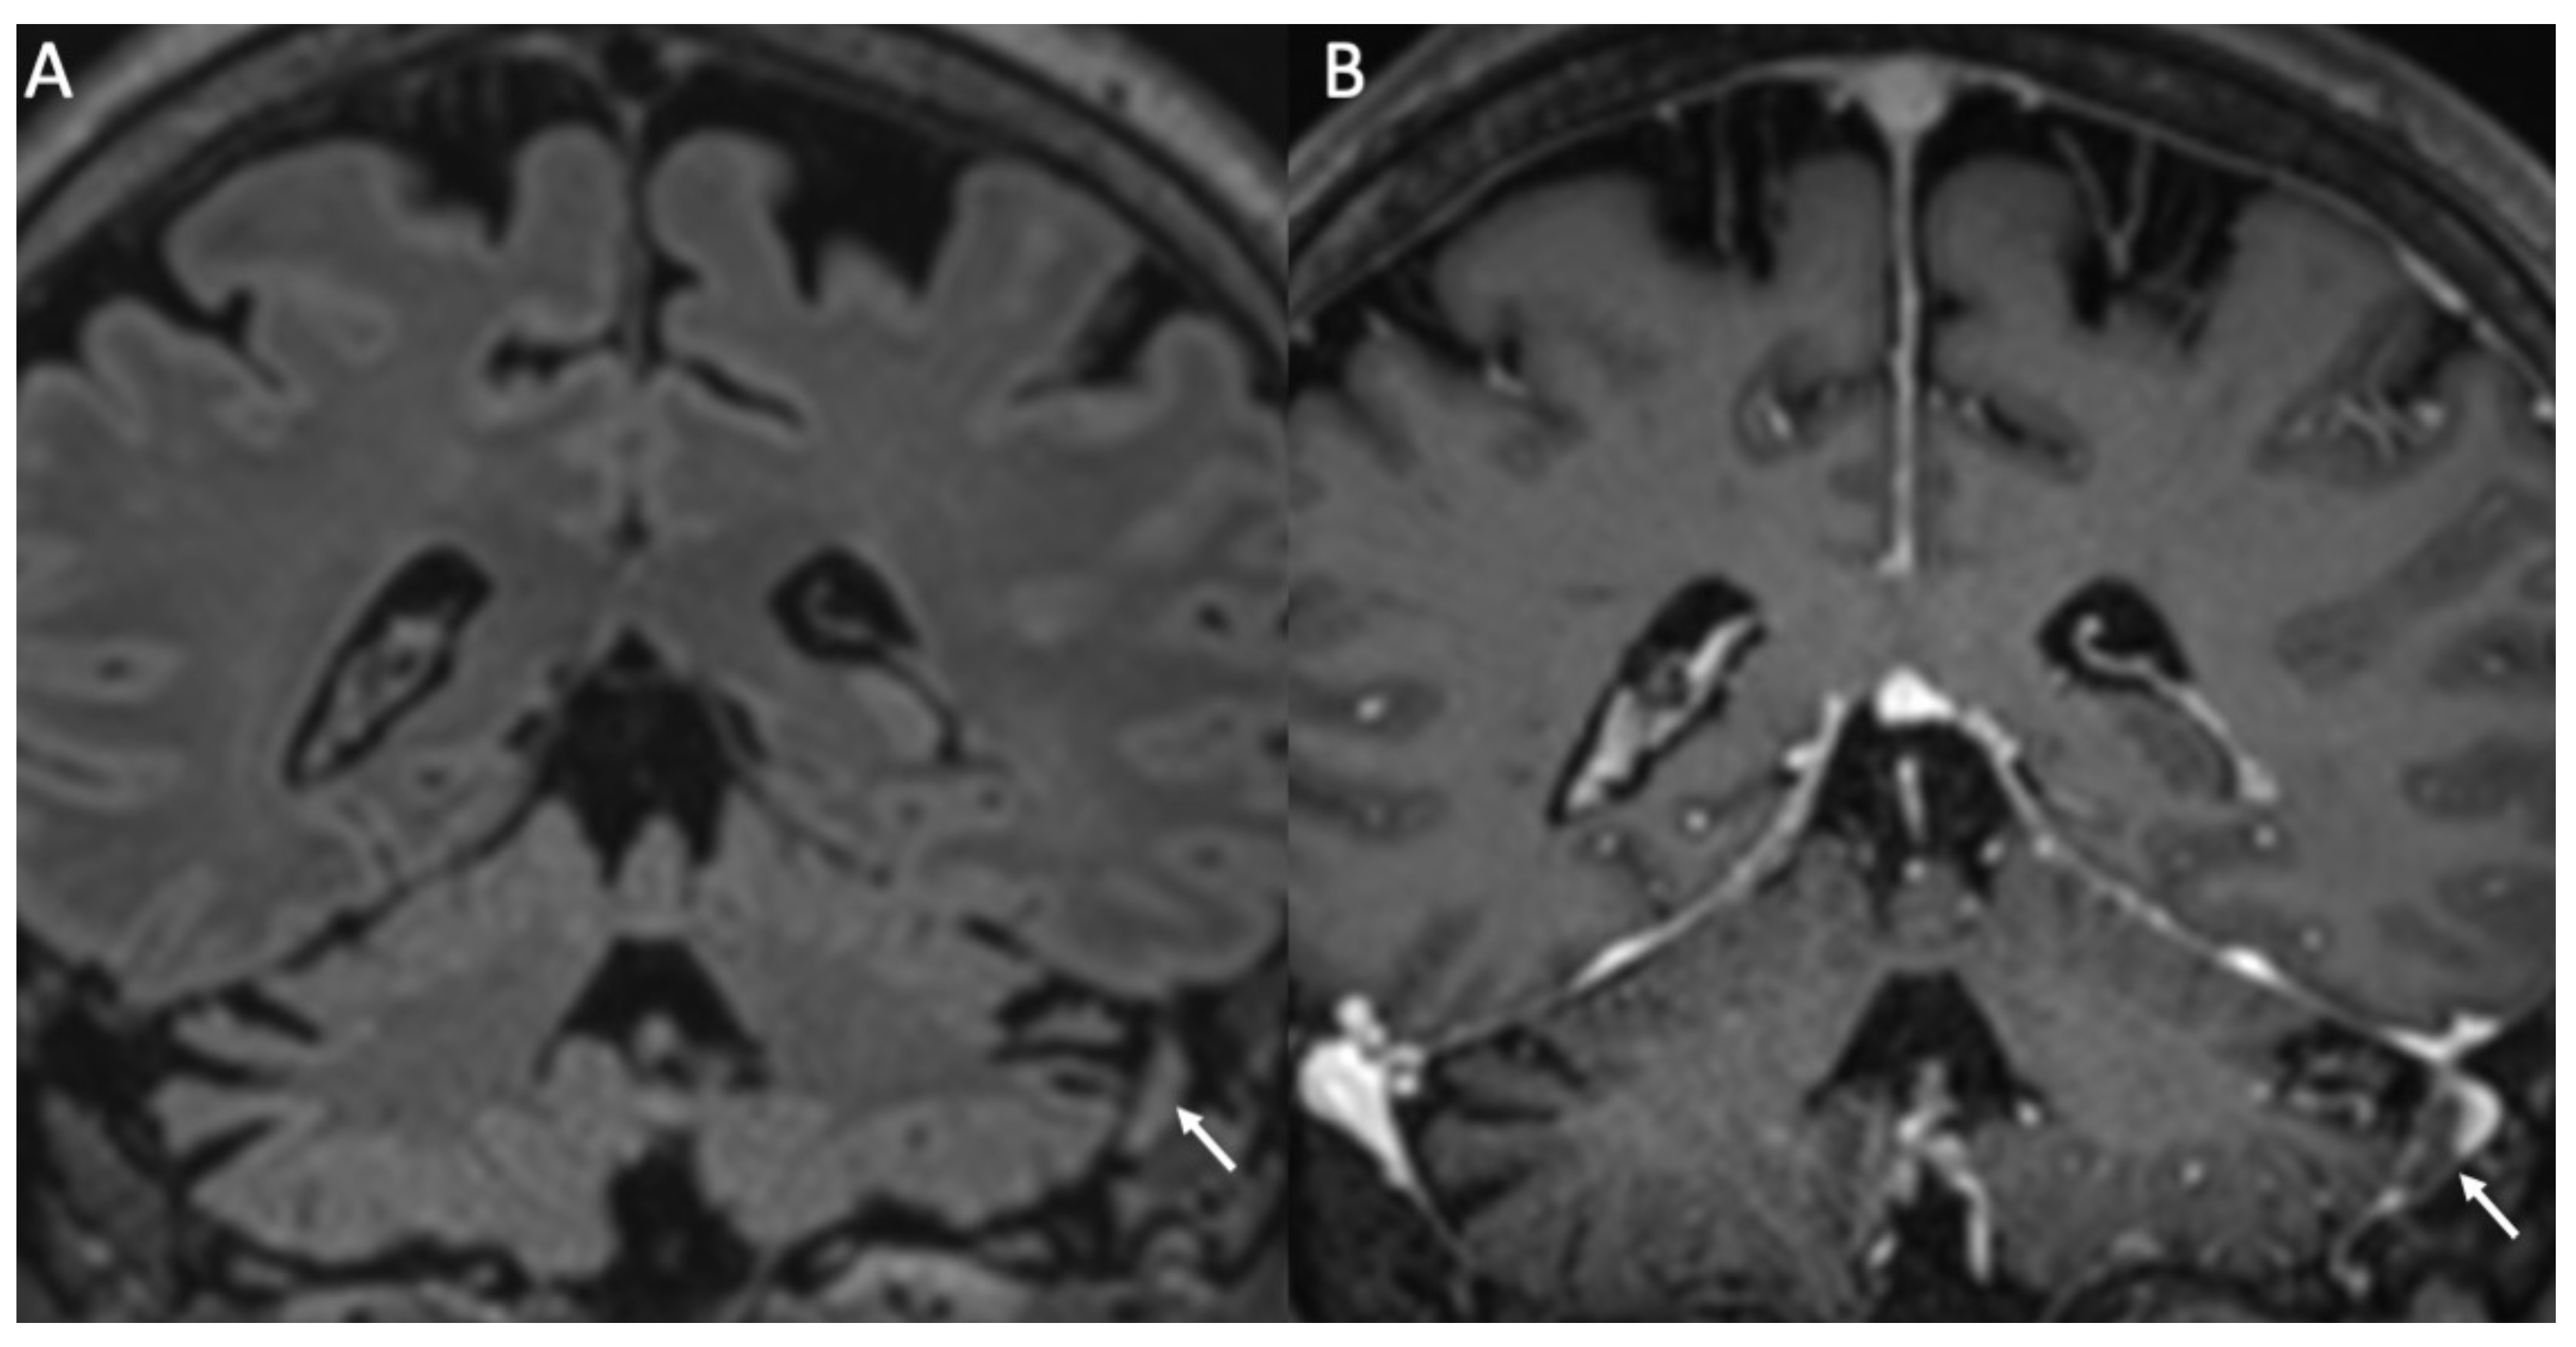

Figure 7.

Coronal FLAIR (A) and enhanced T1 (B) show thrombosis of the right sigmoid sinus in a patient with Streptococcus pneumoniae meningitis (arrows in A,B).